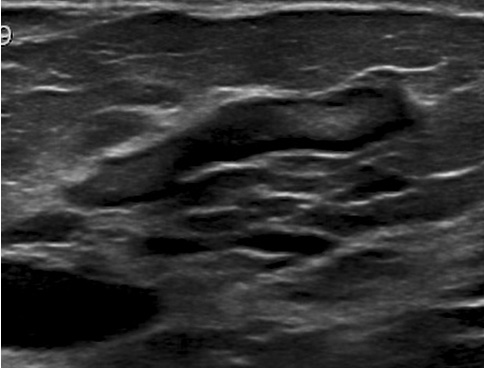

Ectasie Canlaire Solitaire

- Rare

ductal duct ectasia canal canalaire ectasiante

Ectasie Canlaire Solitaire

ductal duct ectasia canal canalaire ectasiante